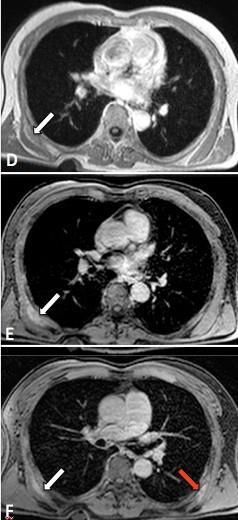

Fig. 3: Nelle immagini T1-dipendenti (D) e T1-dipendenti con soppressione del segnale del tessuto adiposo (E-F), eseguite dopo infusione ev di mdc, la lesione mostra un enhancement disomogeneo e progressivo (freccia). Nelle acquisizioni più tardive dopo mdc (F) è possibile rilevare una sottile patologica impregnazione anche in sede analoga sin. (freccia rossa), reperto che suggerisce una bilateralità della lesione.

Dopo somministrazione ev di mdc, l’enhancement della lesione appare discreto e disomogeneo, progressivo, di tipo  striato e con persistenza di accumulo nelle acquisizioni più tardive (Fig. 3).

striato e con persistenza di accumulo nelle acquisizioni più tardive (Fig. 3).